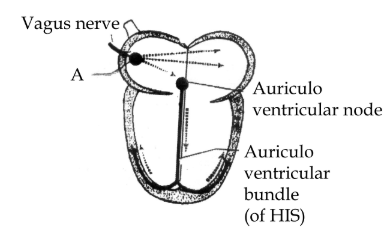

36. Identify A in the diagram given below and state its function

Ans:

- A- Sinu auricular node.

- It initiates and regularises the heartbeat. Therefore, it is also called the pacemaker.